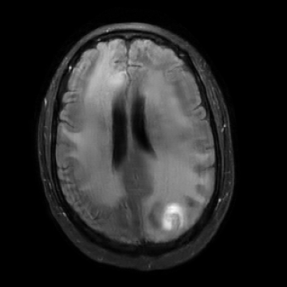

Here, we employ the fastMRI+ dataset to assess our approach’s image reconstruction capability. For the training phase, we employ the original fastMRI brain dataset, which excludes lesion cases, as the basis for training all methods. During the testing phase, however, we utilize the lesion dataset. Table II shows the results, where our method reports the highest PSNR and SSIM values compared to other baselines. It is important to highlight that, unlike the cases of additive k-space noise and training/testing sampling protocol and undersampling rate disparities, the improvements observed from utilizing our method with unseen lesions are somewhat marginal as seen from the average PSNR and SSIM results (at least 1.2 dB PSNR improvement when compared to the 2nd best results). Additionally, visualizations are provided Figure 13 where we highlight the nonspecific white matter lesion area. As observed, both visually and in terms of PSNR values, our approach reports improved results when compared to the other baselines.

In Figure 14, we report results (PSNR in the y-axis) of our method (labeled as ‘Ours’ and ‘Ours DDIM’) and baselines using measurements with unseen lesions combined with worst-case additive noise (generated by the PGD method) with budget indicated in the x-axis. We include these results to evaluate our method and baselines using a scenario that combines multiple sources of instabilities. As observed, our methods report the best results.